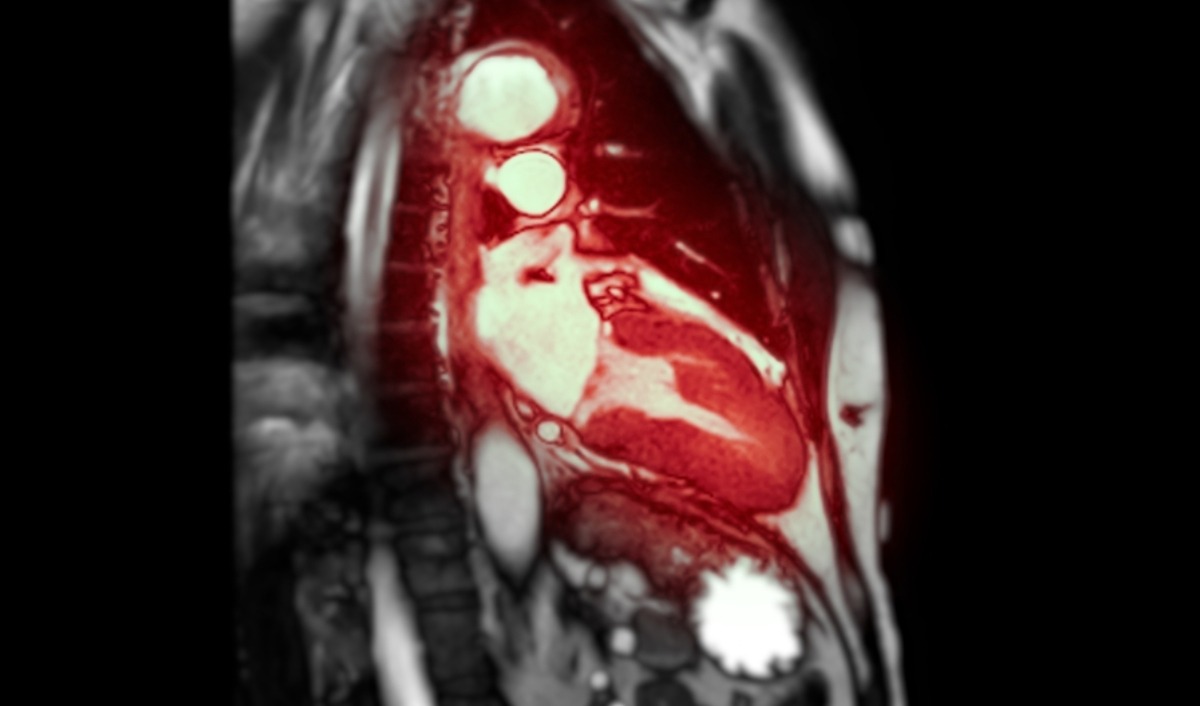

Xạ hình SPECT (Single Photon Emission Computed Tomography) là kỹ thuật ghi hình cắt lớp đơn photon phổ biến nhất, sử dụng camera gamma quay quanh lồng ngực để thu nhận tín hiệu từ chất phóng xạ đã tiêm vào máu. Phương pháp này cho phép bác sĩ quan sát hình ảnh 3D về dòng máu nuôi tim, giúp phát hiện các vùng có lưu lượng máu thấp khi nghỉ ngơi hoặc vận động và xác định mô sẹo sau nhồi máu. Nếu kết quả hiển thị bình thường ở cả hai trạng thái, điều đó khẳng định dòng máu qua các động mạch vành ổn định. Ngược lại, sự thiếu hụt chất đánh dấu trên hình ảnh (điểm lạnh) là bằng chứng của tắc nghẽn hoặc tế bào cơ tim đã chết.

Xạ hình PET (Positron Emission Tomography) là kỹ thuật ghi hình cắt lớp bằng bức xạ positron, cung cấp hình ảnh có độ phân giải và độ chính xác cao hơn so với SPECT trong việc đánh giá chức năng cơ tim.

Thời gian nhận kết quả thường dao động 2 – 4 giờ sau khi hoàn tất quy trình ghi hình cuối cùng. Trong một số trường hợp thực hiện tại các bệnh viện lớn hoặc khi cần hội chẩn chuyên sâu, kết quả có thể được trả trong vòng 24 giờ làm việc. Khoảng thời gian này để kỹ thuật viên xử lý dữ liệu thô từ máy SPECT/PET và bác sĩ y học hạt nhân tiến hành phân tích, đối chiếu giữa hai bộ ảnh trạng thái gắng sức và nghỉ ngơi.